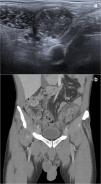

Carcinoma embrionario puro de testículo: presentación de un nuevo caso y revisión de la literatura

Pure embryonal carcinoma of the testis: A new case report and review of the literature